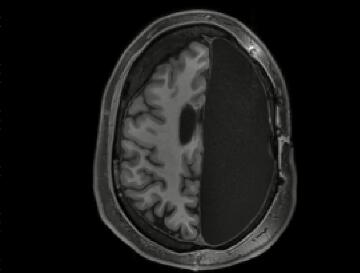

磁共振成像扫描,是在儿童时期由于癫痫而切除了整个半球的成年人大脑的一部分。视频由加州理工学院脑成像中心信用

当进行半球切除术的人进行大脑扫描以进行研究时,他们的行为就好像其他典型的成年人一样,握着克利曼博士的手,然后闲聊。但是磁共振成像(MRI)的结果表明,这些人的童年时期大脑的一半被切除了。

加州理工学院的认知神经科学家,研究的合著者拉尔夫·阿道夫斯(Ralph Adolphs)说:“每当研究他们的大脑扫描时,我们都会说,'哇,这个大脑真的不应该起作用。' 。“如果您采用的任何其他系统都具有多个部分,这些部分的功能都相互依赖,例如心脏,并且将其分成两半,那么它将无法正常工作。您拿起我的笔记本电脑,将其切成两半,将无法使用。”